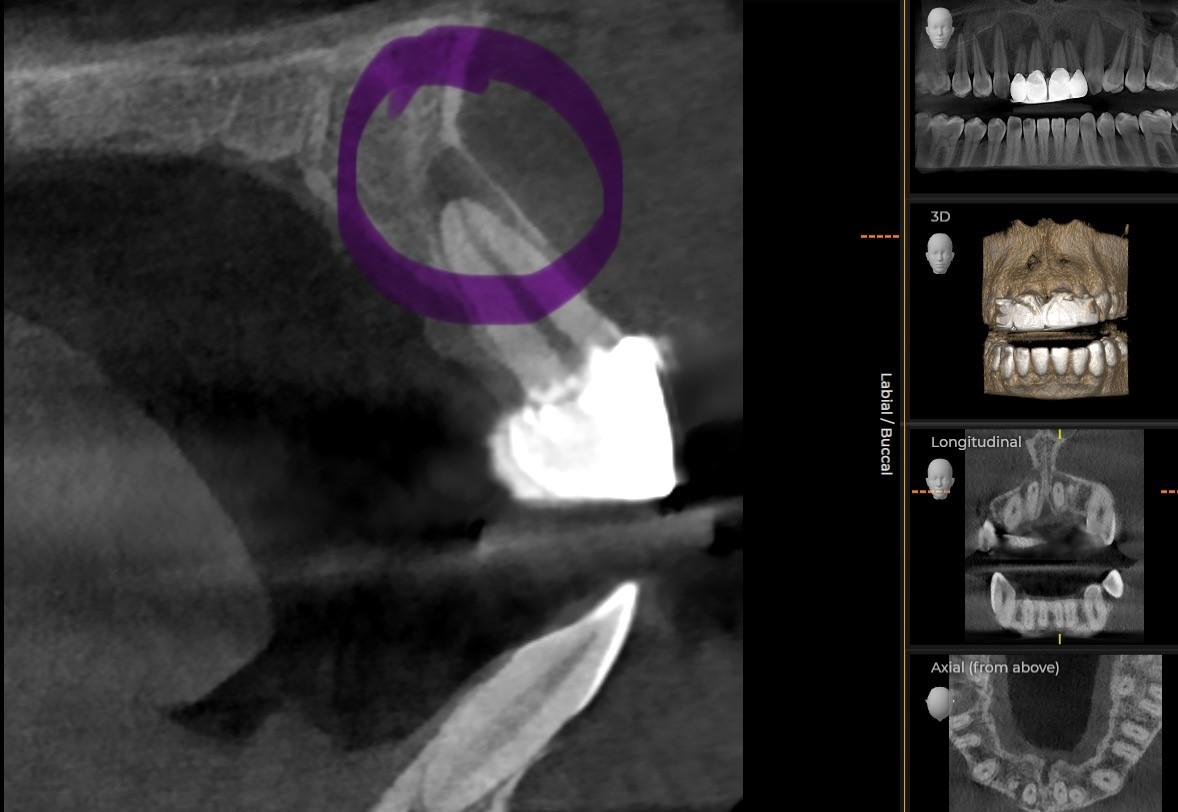

CBCT Scans London: Why they are a Game-Changer in Dentistry At Optimal Dental Health, we’re always striving to stay at